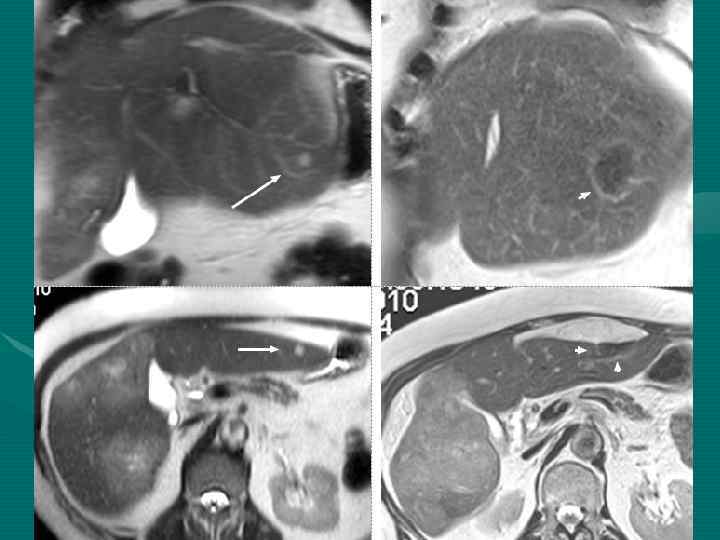

МРТ диагностика с ПРИМОВИСТОМ